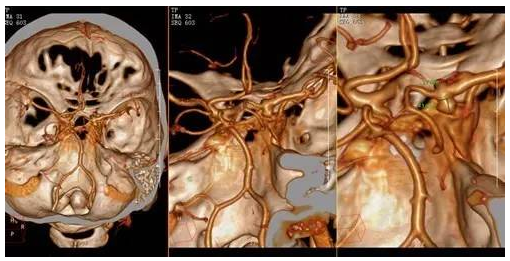

张某某,女,51岁, 早上起床对镜子梳头突然出现右边太阳穴疼痛,还有右眼睑下垂,以为是没有睡好就没有多理会,还和爱人开玩笑,人老了皮都下垂了,这种情况持续5天,一天比一天重,遂来院就诊。查体:右侧睑裂0.2cm,右侧瞳孔直径3.5mm,对光反射消失。头颅CTA示右侧后交通动脉瘤,瘤体长约4.1mm,瘤颈宽约3.7mm,未见蛛网膜下腔出血。诊断:右侧后交通动脉瘤。

术前▲